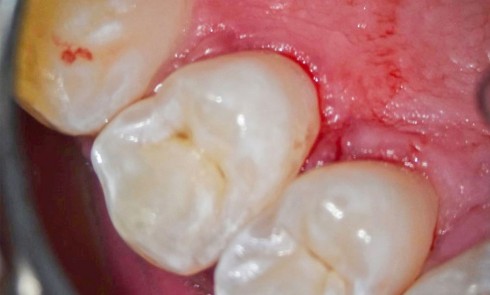

Article réservé à nos abonnés Les techniques invasives pour le traitement des lésions carieuses modérées à étendues

Définition d’un matériau bio-interactif Larry Hench a décrit un matériau bioactif (MBA) [1] comme un matériau qui induit une réponse...